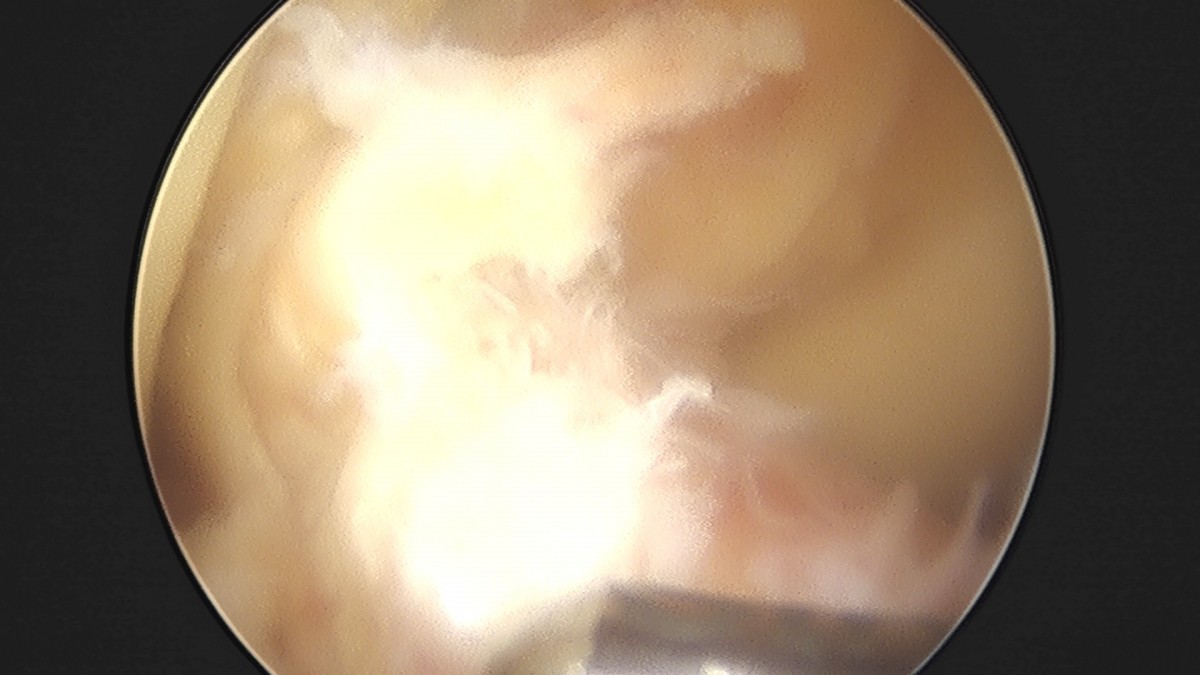

이재상원장님 무릎 전방십자인대 재건술 김태O 환자

작성자 최고관리자 댓글 0건 조회 679회 작성일 25-09-16 16:23